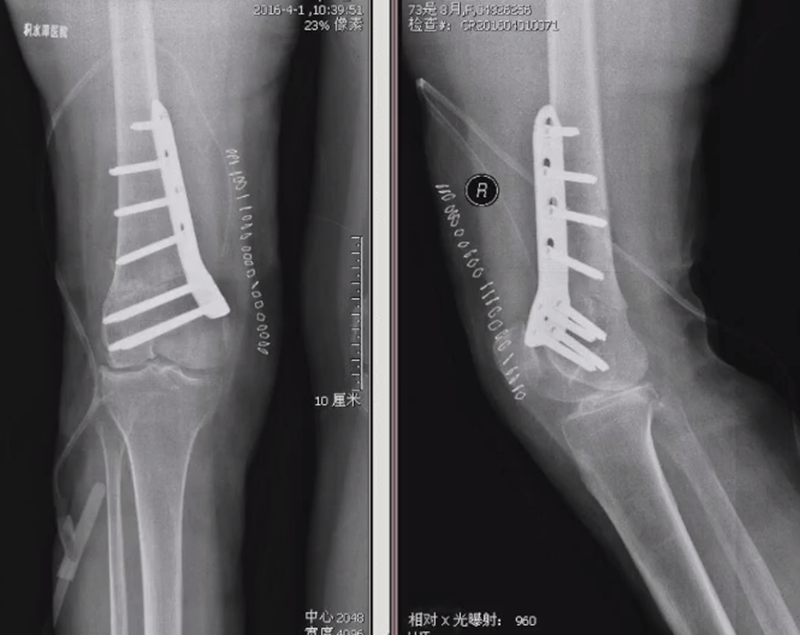

病例,X患者,女,双侧外翻膝,行双侧DFO。

术后6周摔伤,一侧出现膝内翻。

影像学检查显示左侧出现合页断裂。

进行翻修,术前力线显示内翻。

术中发现螺钉松动,截骨端出现坎插迹象。

近端螺钉松开,调整力线,重新固定后,在外侧加小钢板抗旋。

术后10周复查,力线较好。